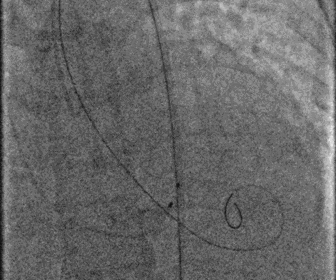

股动脉造影

图片